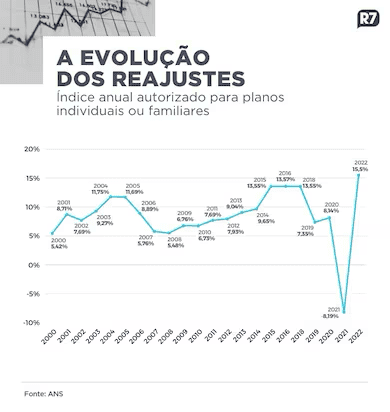

Planos de saúde coletivo terão aumento de 14% em terceiro ano de alta

De acordo o levantamento, o mercado tem sido pressionado por aumentos de preços acima de 15% desde meados de 2023

Os planos de saúde coletivos terão reajuste de dois dígitos neste ano, de acordo com relatório da XP Investimentos com dados da ANS (Agência Nacional de Saúde Suplementar). O aumento médio foi de 15% no período entre dezembro de 2023 e fevereiro de 2024.

De acordo com o levantamento, os reajustes se mantêm nesse patamar pelo terceiro ano seguido. Em 2023, a alta média nos preços de planos coletivos foi de 14,38%; em 2022, os reajustes oscilaram na casa de 11,54%.

Os reajustes dos planos individuais e familiares são limitados pela agência, que fixa um teto.

Novo reajuste deve ser definido no mês de maio (Arte/R7)